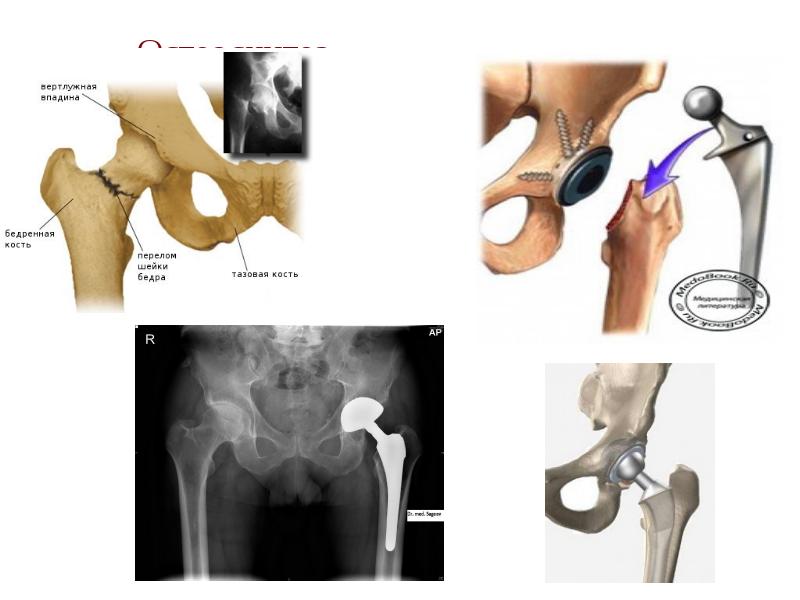

- 6. Остеопороз Остеопороз (от остео…и греч. Póros - отверстие, пора) -

- 7. Остеосинтез